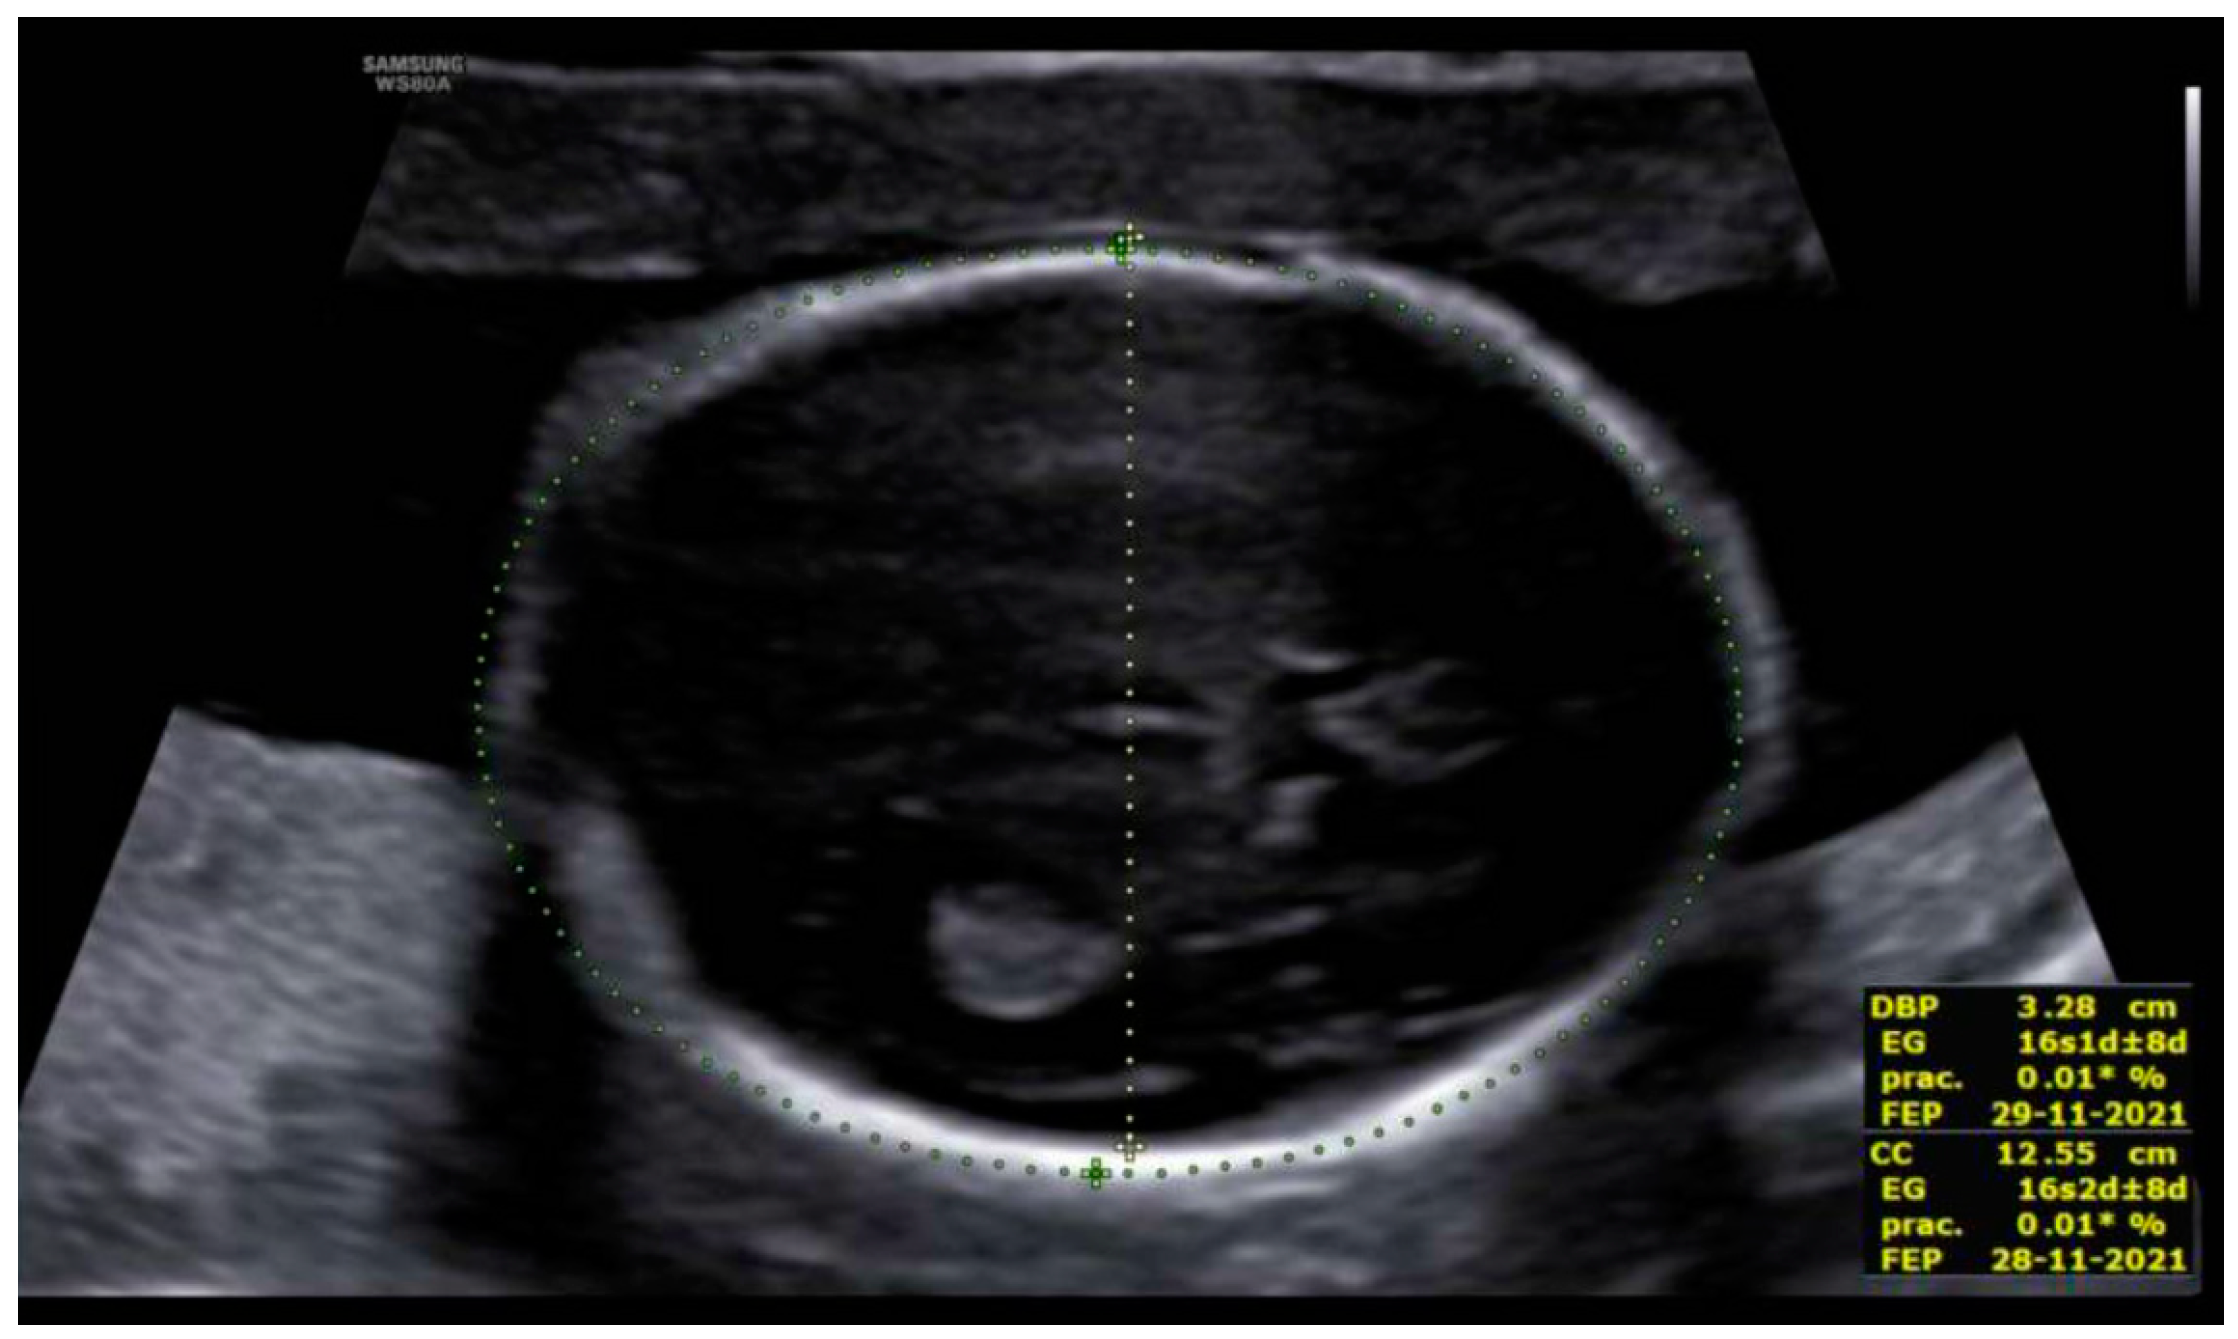

3. Results: Case Presentation

| Microcephaly | 85% | Yes | No |

| Agenesis/hypoplasia of CC | 36% | Yes | No |